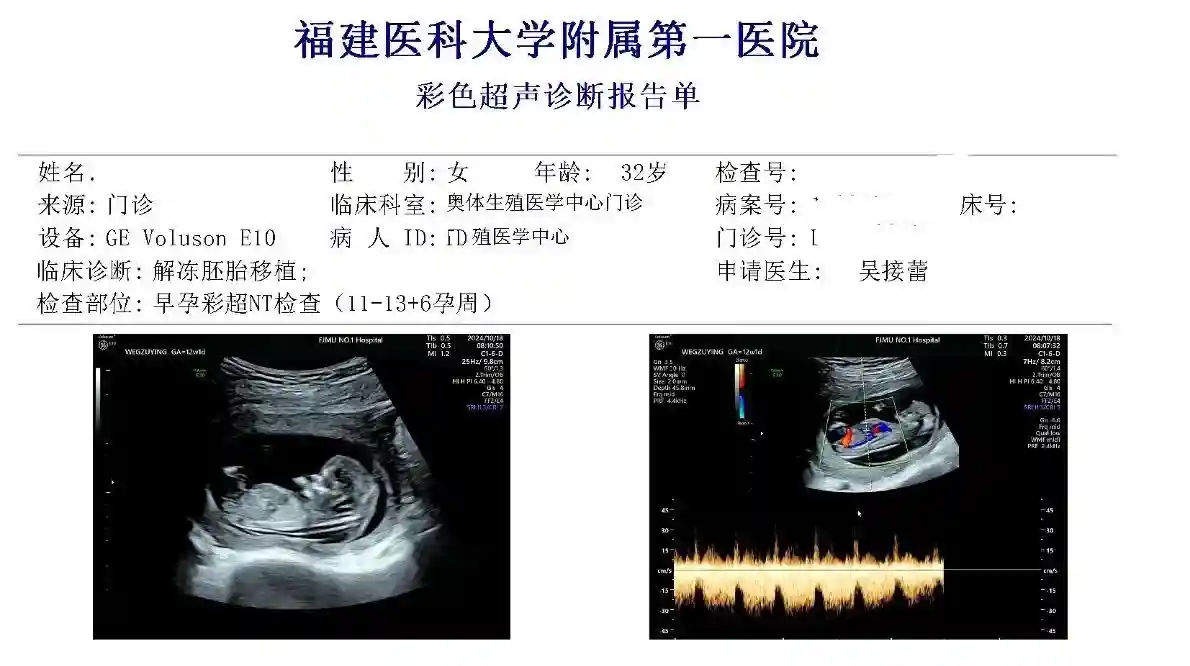

#试管之路 #一代试管 #nt通过 #省妇幼 #福建省医科大学附属第一医院

2024年的1月开始调理-10.18日nt毕业了!